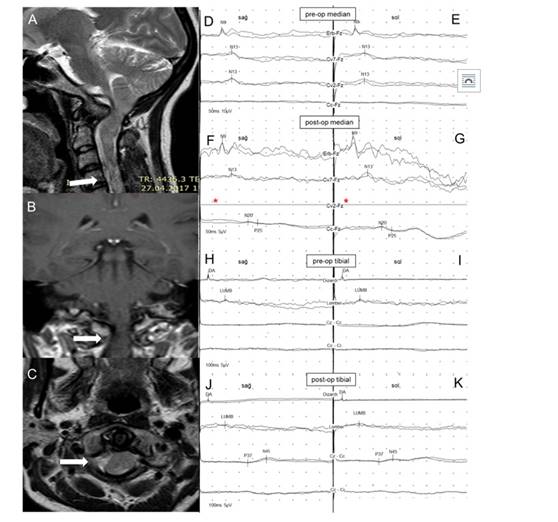

Şekil 17. Kranyovertebral bileşke anomalisi

olan 36 yaşındaki kadın hastanın MR kesitleri (A, B, C), pre- (D, E) ve post-op (F, G) median SEP

incelemeleri ile pre- (H, I) ve post-op (J,

K) tibial SEP incelemeleri. Pre-op incelemelerde

sağ ve solda hem median hem de tibial kortikal potansiyellerin kayıp olduğu

görülmektedir. Post-op erken dönemde düşük amplitüdlü

de olsa tüm kortikal potansiyeller elde edilmiştir. *Ameliyat kesisi nedeniyle C2 elektrodu

yerleştirilememiştir (Hasta Prof.

Dr. Faruk Ünal tarafından ameliyat edilmiştir).